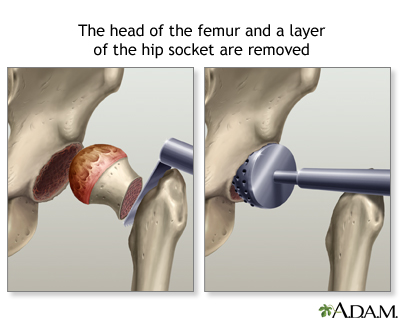

After you receive anesthesia, your surgeon will make a surgical cut to open up your hip joint. This cut is often over the buttocks or the side of your hip. Then your surgeon will:

- Cut and remove the head of your thigh bone.

- Clean out your hip socket and remove the rest of the cartilage and damaged or arthritic bone.